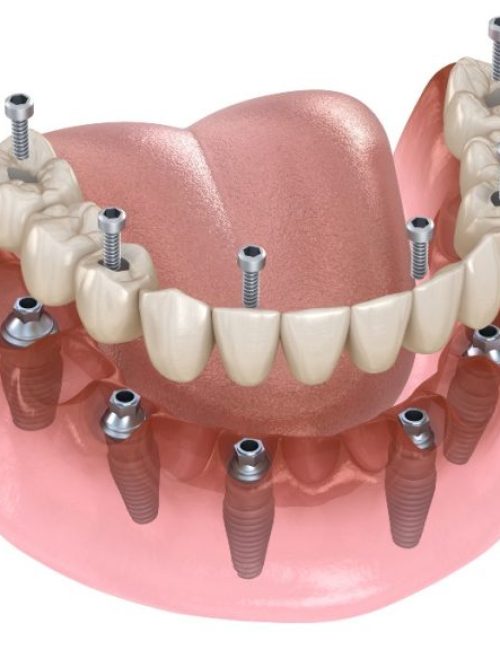

Protesi fisse su impianti

Le protesi fisse su impianti possono essere sostenute da un minimo di 4 impianti ad un massimo di 10 / 12 impianti con una struttura metallica di rinforzo.